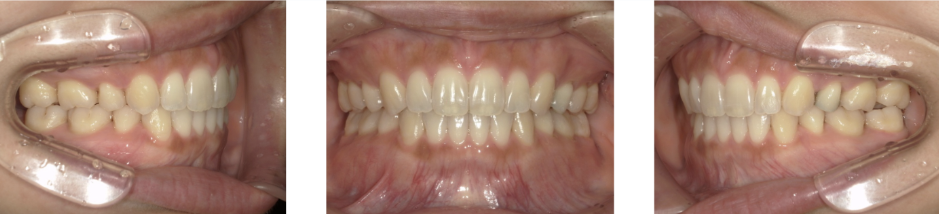

Before Photo

Before

After Photo

After

主訴

出っ歯 口元が出ている

治療期間

1年10か月

料金

相談料0円、検査料33,000円、動的矯正治療費990,000円、調整料110,000円、保定装置料5,500円x5枚(必要枚数)

治療概要

上下の個々の歯の大きさに対して、上下の顎が共に小さく、歯が並ぶ余地が不足したために、前歯が押し出されて出っ歯が生じている。

改善には、上下左右の第一小臼歯を抜歯して空隙を作り、前歯を後退させた。

矯正での歯の移動のリスクとして歯根吸収、歯肉退縮、歯髄怪死が考えられます。

保定装置の装置を怠ると隙間が生じてくる可能性があります。